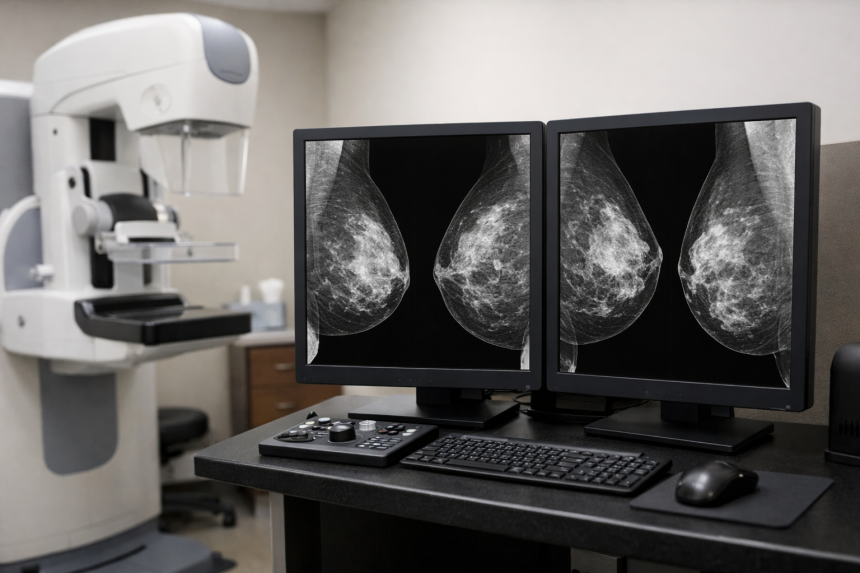

Mammografia z AI w Szwecji może pomóc wcześniej wykrywać agresywne postacie raka piersi i jednocześnie zmniejszać obciążenie pracy lekarzy – wynika z dużego badania prowadzonego na Uniwersytecie w Lund. O efektach programu MASAI piszą m.in. Euronews oraz naukowcy publikujący wyniki w The Lancet.

Badanie MASAI dotyczyło wsparcia radiologów narzędziem opartym na sztucznej inteligencji, które zaznaczało podejrzane obszary na zdjęciach mammograficznych. Według opisu w Euronews AI miała pełnić rolę narzędzia pomocniczego, a decyzję końcową podejmował radiolog.